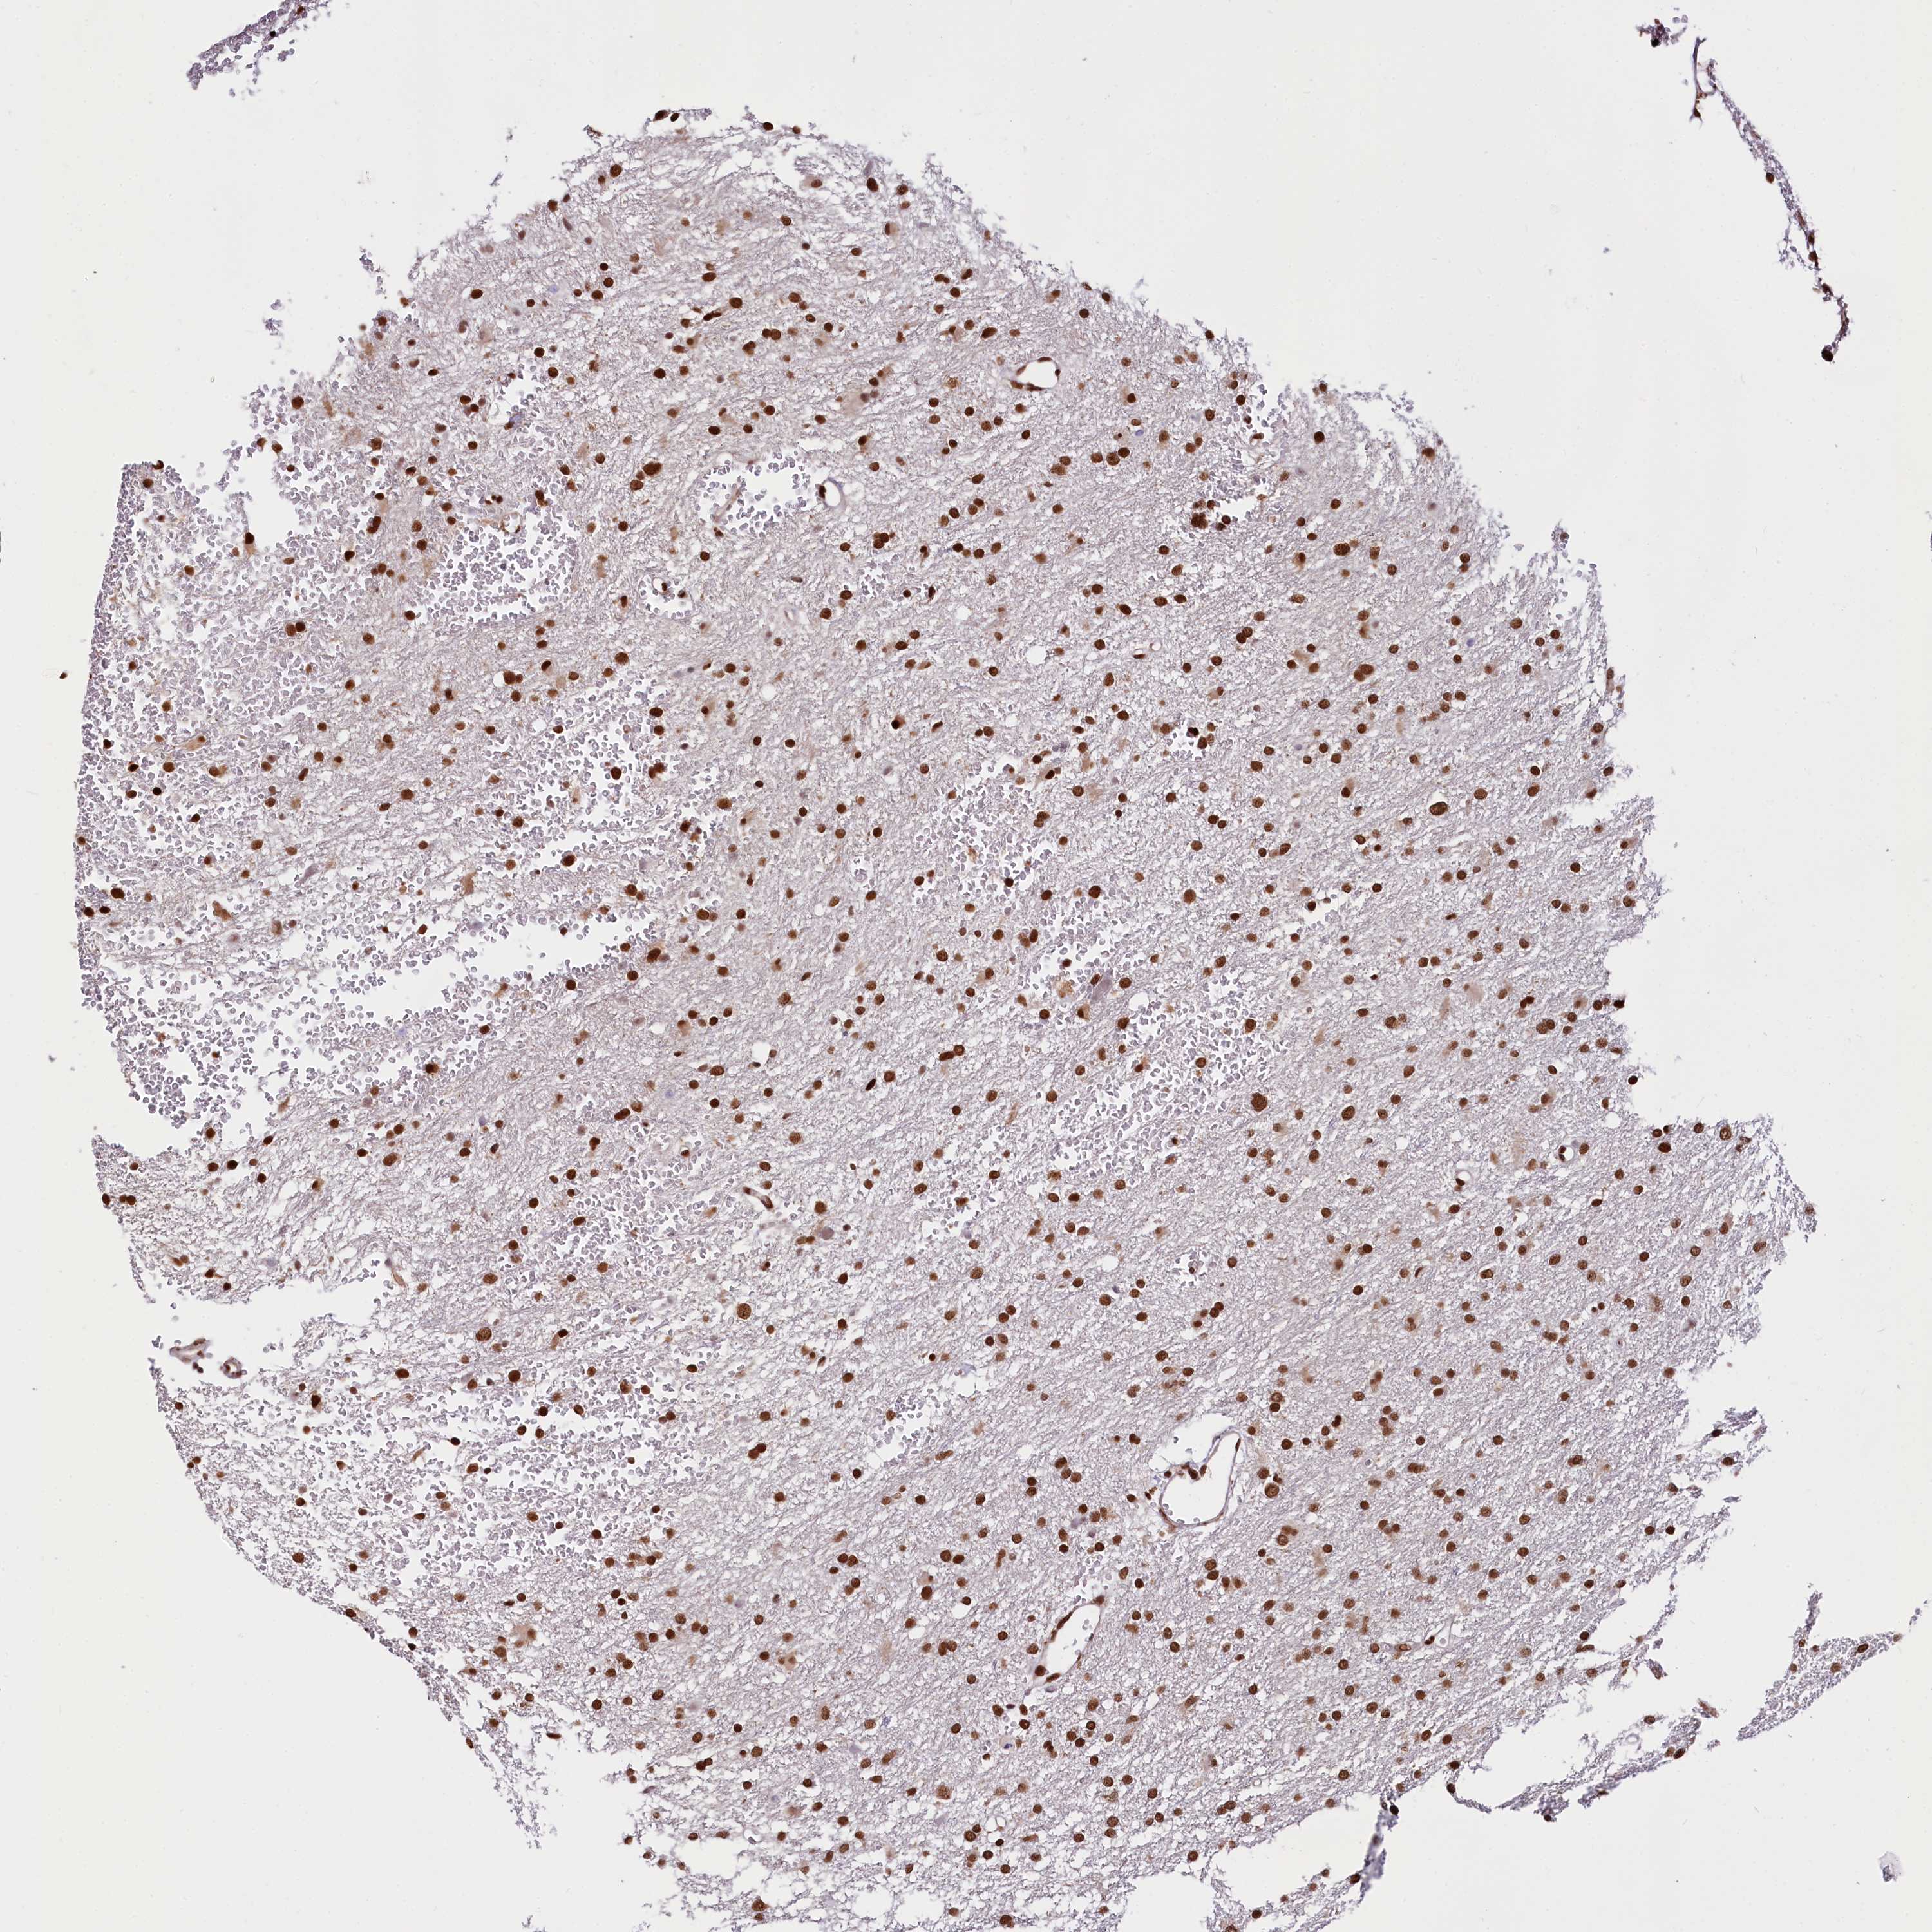

GLIOMA - Protein expressioni

A mouse-over function shows sample information and annotation data. Click on an image to view it in a full screen mode. Samples can be filtered based on level of antibody staining by selecting one or several of the following categories: high, medium, low and not detected. The assay and annotation is described here.

Note that samples used for immunohistochemistry by the Human Protein Atlas do not correspond to samples in the TCGA dataset.

Antibody stainingi

Antibody staining in the annotated cell types in the current human tissue is reported as not detected, low, medium, or high, based on conventional immunohistochemistry profiling in selected tissues. This score is based on the combination of the staining intensity and fraction of stained cells.

Each image is clickable and will lead to virtual microscopy that enables deeper exploration of all samples and also displays staining intensity scores, fraction scores and subcellular localization as well as patient and tissue information for each sample.

Antibody HPA039513

Antibody HPA040015

Staining

High

Medium

Low

Not detected

Intensity

Strong

Moderate

Weak

Negative

Quantity

>75%

75%-25%

<25%

None

Location

Nuclear

Cytoplasmic/membranous

Cytoplasmic/membranous,nuclear

Glioma, malignant, High grade

Glioma, malignant, Low grade